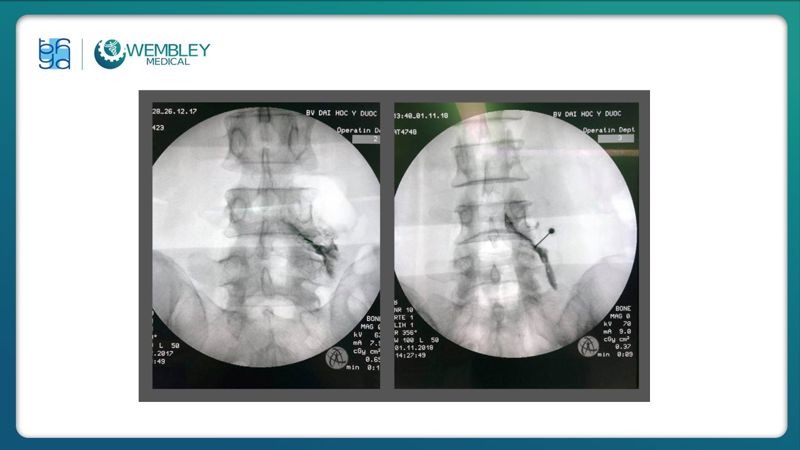

Huyết tương giàu tiểu cầu (PRP) ngày càng được ứng dụng rộng rãi trong điều trị đau mạn tính nhờ khả năng hỗ trợ tái tạo mô và giảm viêm hiệu quả.

Trong bài báo cáo tại Hội thảo VAI TRÒ CỦA HUYẾT TƯƠNG GIÀU TIỂU CẦU TRONG ĐIỀU TRỊ BỆNH LÝ CƠ XƯƠNG KHỚP (26/07/2025), TS.BS. Lê Viết Thắng - Trưởng Đơn nguyên Điều trị đau, Khoa Ngoại Thần kinh, Bệnh viện Đại học Y Dược TP.HCM đã chia sẻ những góc nhìn chuyên môn, kinh nghiệm lâm sàng và đánh giá thực tiễn về hiệu quả của PRP trong điều trị đau mạn tính, góp phần làm rõ vai trò của PRP trong chiến lược điều trị hiện đại, an toàn và cá thể hóa cho người bệnh.